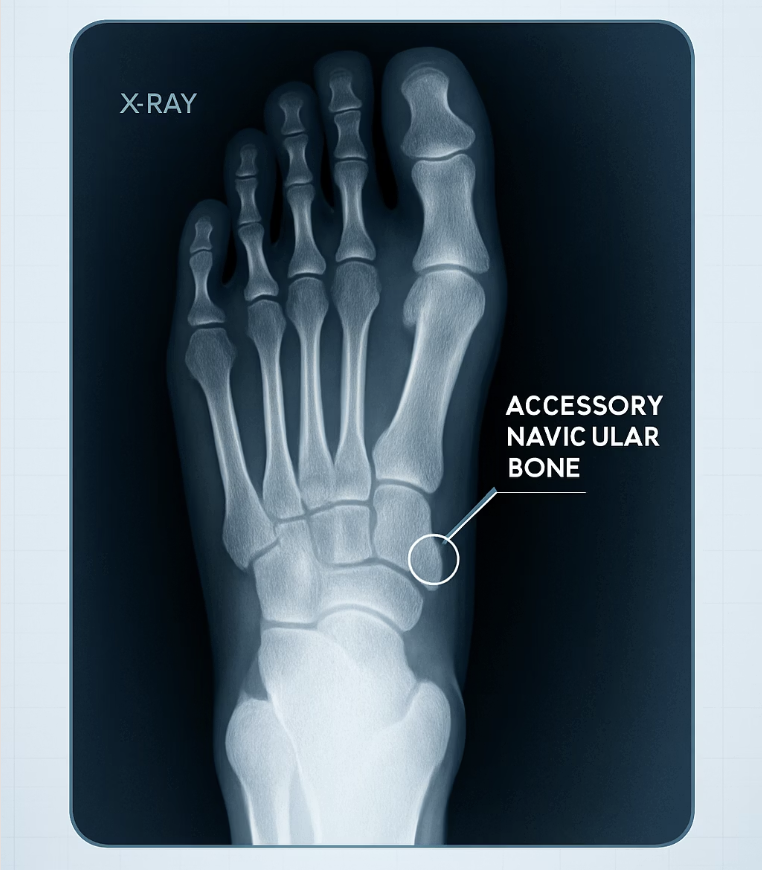

단순 염좌가 아닐 때, 숨어있는 보너스 뼈

특히 발 안쪽 복숭아뼈 바로 아래가 툭 튀어나와 있고, 그 부위를 누르면 통증이 심하다면 ‘부주상골 증후군’을 의심해 볼 수 있습니다. 부주상골은 일부 사람들이 선천적으로 가지고 태어나는 ‘없어도 되는 덤 뼈’입니다. 평소에는 아무 문제 없다가, 발에 꽉 끼는 신발을 신거나 과격한 운동을 하면서 이 덧뼈에 붙어있는 힘줄이 자극을 받아 염증이 생기는 것이죠.

이 경우, 통증을 유발하는 가장 큰 원인은 ‘마찰’과 ‘압박’입니다. 따라서 발 안쪽을 강하게 압박하는 신발을 피하고, 발바닥의 아치를 받쳐주는 기능성 깔창을 사용하여 덧뼈에 가해지는 부담을 줄여주는 것이 효과적인 해결책입니다. 통증이 지속된다면 정확한 진단을 위해 병원을 방문하는 것이 좋습니다.